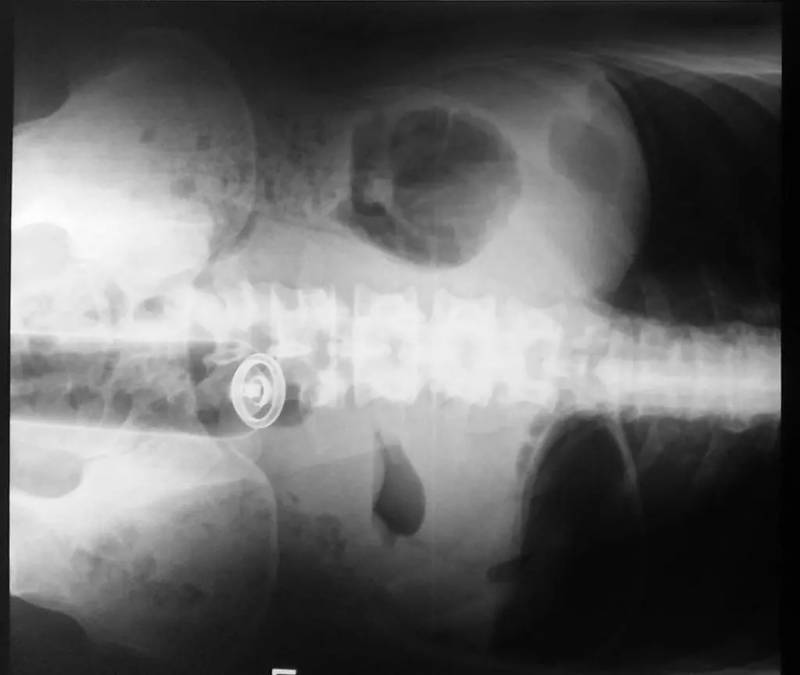

小胡瓜

19厘米長,頂端已經到了膽囊附近,這種病例非常罕見,使得醫生很納悶是怎麼把蔬菜塞進直腸的